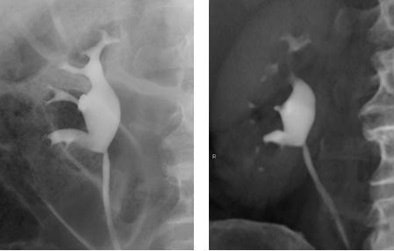

![]() |

| Retrograde pyelogram versus IVU. Left, normal right retrograde pyelogram. Right, single volume-rendered CT image obtained during 64-channel CTU. Images courtesy of Dr. Terri Vrtiska, Mayo Clinic, Rochester, MN. |